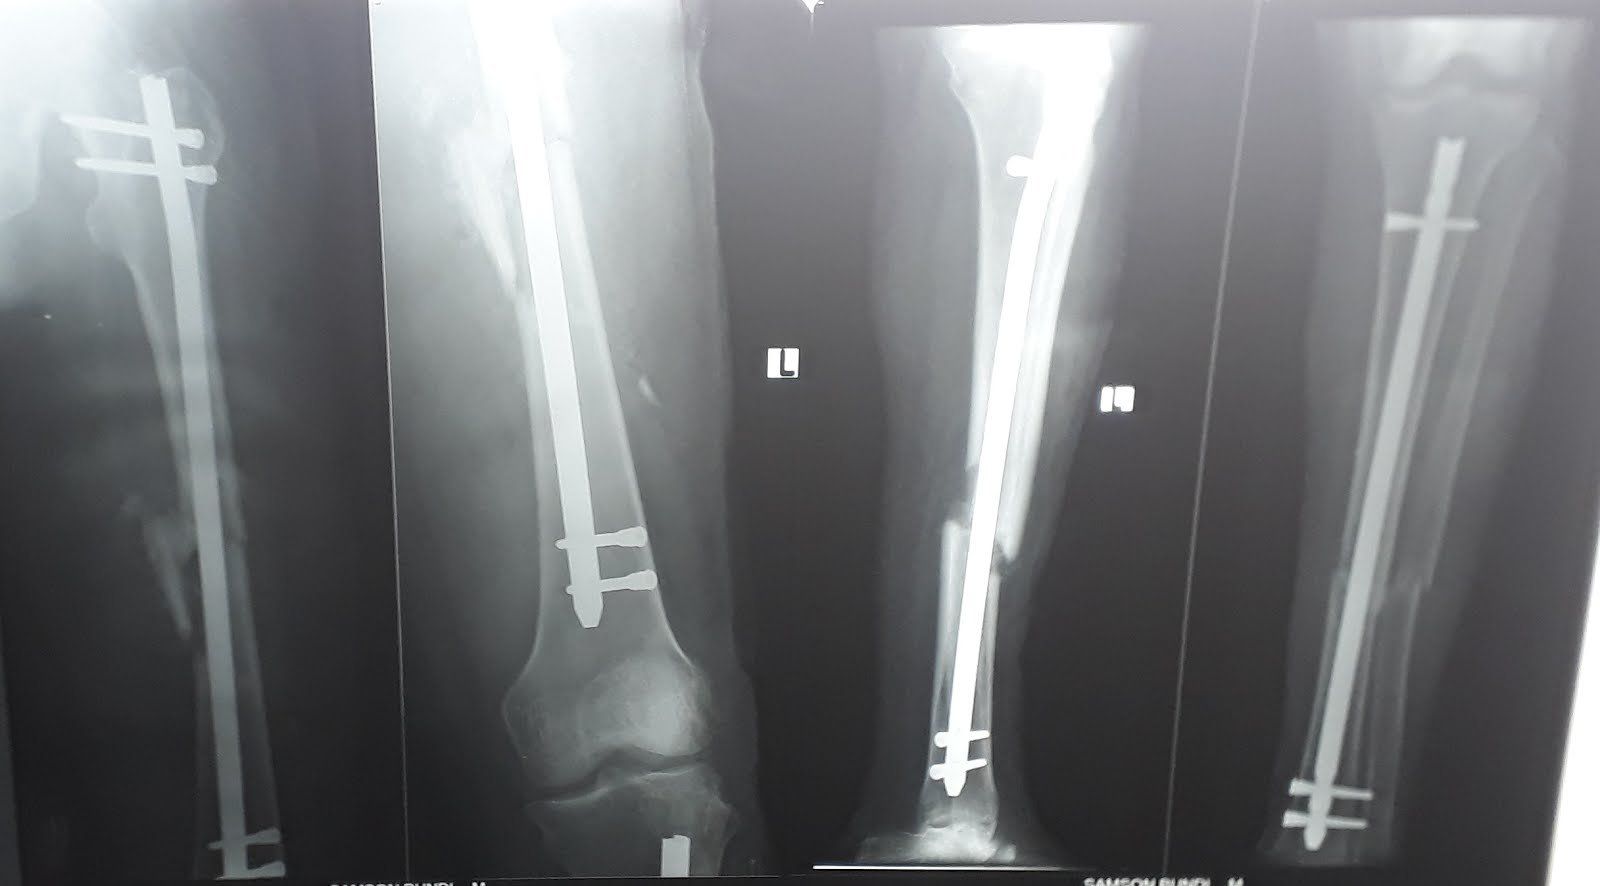

GIOVEDI' ORTOPEDICO

Oggi è stata una giornata estremamente impegnativa dal punto di vista

ortopedico.

L'ambulatorio era affollato sin dal mattino, e la lista operatoria lunga.

Fortunatamente non ci sono stati cesarei ad interrompere il corso

degli interventi.

Con il Dr Wekesa abbiamo fatto grossi interventi che ci hanno tenuti

impegnati fino a molto tardi.

Anche oggi abbiamo aiutato tante persone, con fratture inveterate e complesse.

E' stata una giornata dura anche in ambulatorio ortopedico, con

tantissimi pazienti che sono venuti per le visite di controllo

post-operatorio e per gli appuntamenti per un nuovo intervento.

Tantissimo lavoro, ma anche tanta soddisfazione nel considerare che la

gente si fida di noi e viene a cercare i nostri servizi, anche se

siamo lontani e piuttosto sperduti.

Fr Beppe